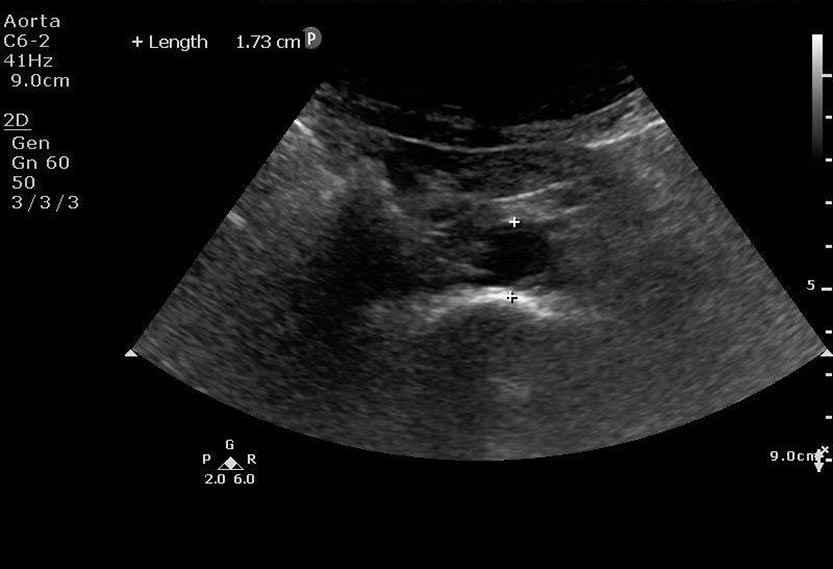

This is a 53 year old female who presents with altered mental status. She is found to have sepsis. Her urinalysis is marginally positive for infection. She is not fluid responsive and does not respond to pressor support. Hydronephrosis is discovered on bedside ultrasound resulting in urology consultation and operative management for source control.